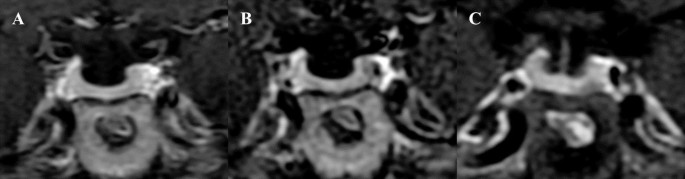

ACTH levels progressively increased as the dose of osilodrostat was escalated (Fig. 2A). After 3 months of biochemical eucortisolism, she underwent Met-PET/MRCR, which revealed a distinct methionine-avid lesion in the right posterolateral aspect of the sella (Fig. 3). Imaging was performed as previously reported [7, 8, 14]. Conventional MRI findings remained stable, with no new abnormalities. As she remained clinically and biochemically eucortisolemic on osilodrostat, glucocorticoid supplementation was not required pre- or perioperatively.

11C-Methionine PET/CT coregistered with volumetric MRI (MET-PET/MRCR) following treatment with osilodrostat. A subtle area of reduced gadolinium enhancement can now be appreciated on the right posterosuperior aspect of the gland (A-C). MET-PET/MRCR confirms focal tracer uptake at this site (yellow arrows) and also within normal gland anteriorly (white arrow) (D-F). Three-dimensional reconstruction using CT, MRI, and PET datasets demonstrating the location of the corticotroph microadenoma which was confirmed at subsequent surgery (G-H).